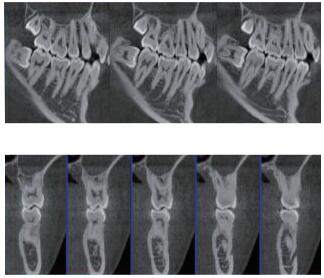

三维重建任意断层

专有三维重建算法,可提供任意位置高清断层影像。

多平面组合重建

可同时观察轴向面、冠状面和矢状面图像,方便临床诊断。